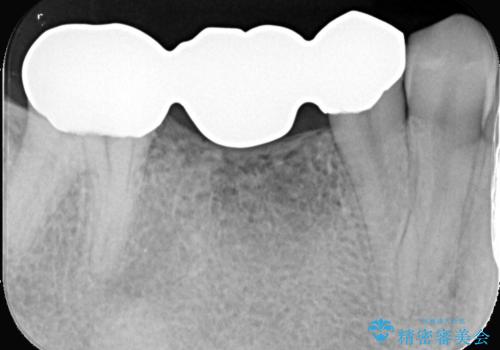

「つながった歯を独立させ、清掃性と耐久性を向上。インプラントとFGGによる機能再建」

ブリッジを外し、欠損している6番にインプラントを埋入。

土台となっていた5番と7番は、セラミッククラウンで修復。

インプラントとセラミック修復: 中央の6番にインプラントを埋入し、両隣の5番・7番はそれぞれ独立したセラミッククラウンで修復しました。ブリッジ時代は歯がつながっていたためお手入れが困難でしたが、個別の歯になったことで、一本ずつフロスが通るようになり、セルフケアの精度が劇的に向上しました。

FGG(遊離歯肉移植術)の実施: インプラントを長持ちさせるためには、周囲に硬く動かない「角化歯肉」が必要です。患者様の上あごから丈夫な歯肉を移植するFGGを行うことで、インプラント周囲に十分な厚みと幅のある角化歯肉を形成しました。